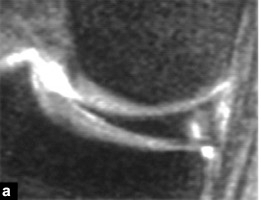

Рисунок 4 Шкала Столлера.а: степень 1: один или несколько промежуточных узловых гиперинтенсивных участков, связанных с суставной поверхностью мениска;б: степень 2: линейная промежуточная гиперинтенсивность на суставной поверхности мениска;c: Степень 3: Линейная промежуточная гиперинтенсивность, распространяющаяся на суставную поверхность мениска.

Степень 1: гиперинтенсивный узловой мениск сохраняется на поверхности мениска;

Степень 2: линейный мениск с высоким сигналом сохраняется на поверхности мениска;

3 степень: гиперинтенсивность распространяется на одну суставную поверхность мениска.